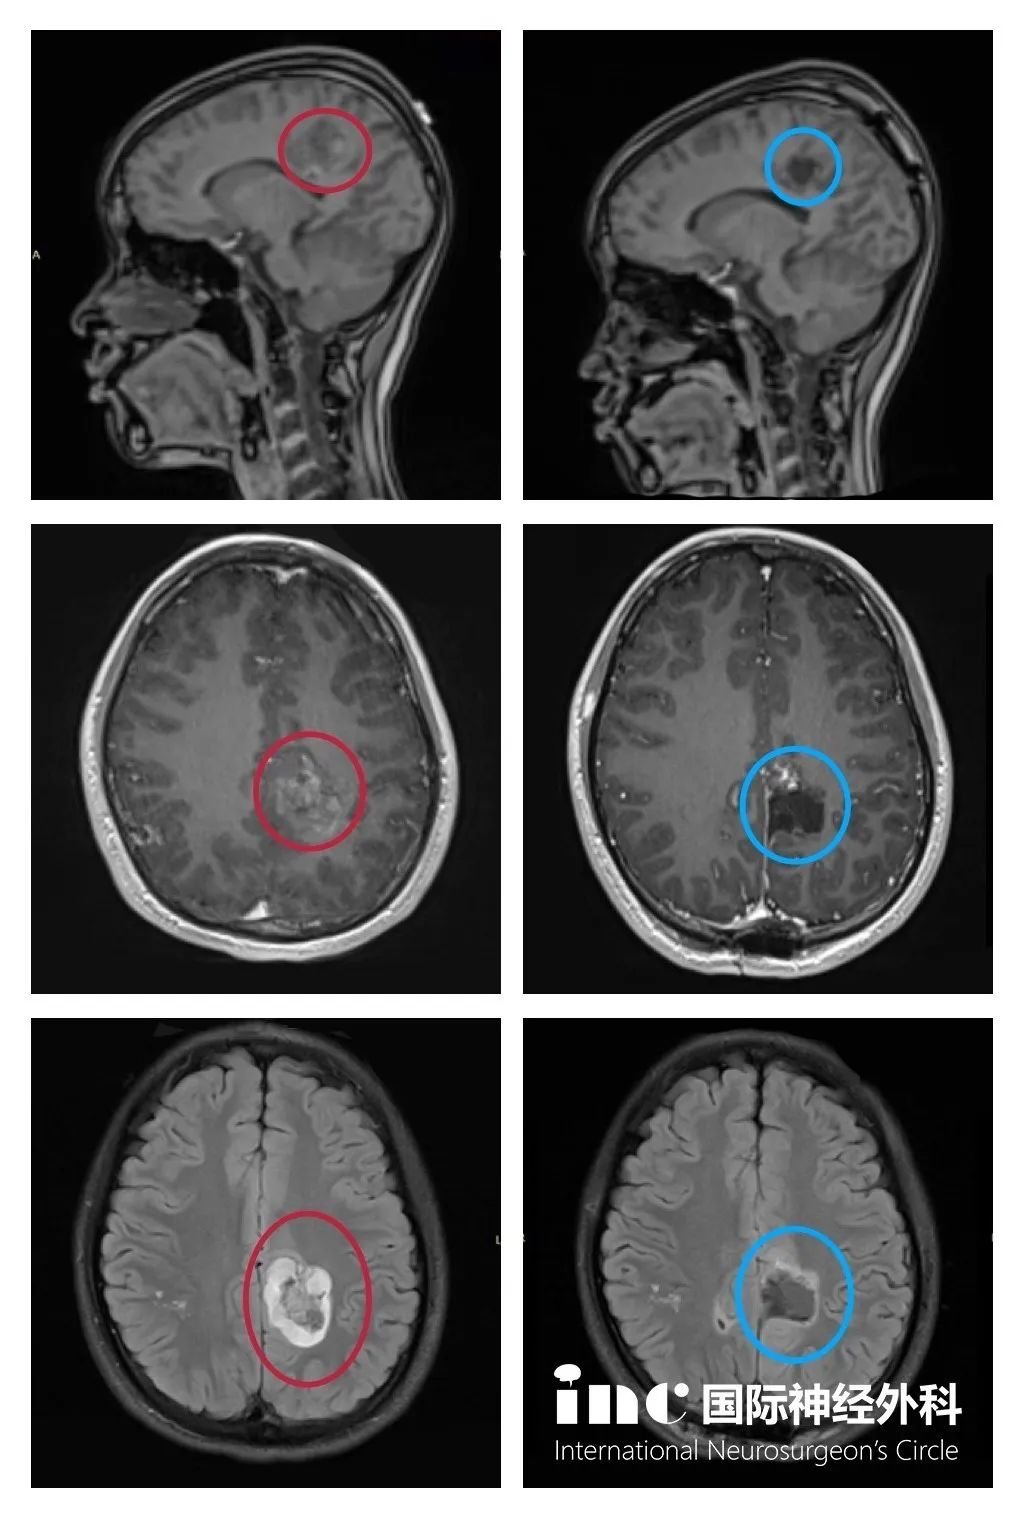

術(shù)前術(shù)后影像對(duì)比

(紅色為術(shù)前,藍(lán)色為術(shù)后)

核磁影像顯示腫瘤全切并沒有復(fù)發(fā),無其他神經(jīng)功能新癥狀。以下為術(shù)后3個(gè)月的MRI影像